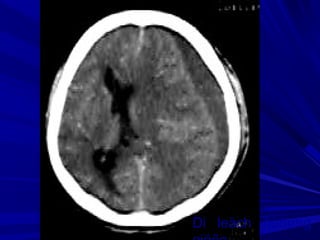

Buøi vaên L., Nam, 45 tuoåi, Xuaát huyeát nhaân beøo-bao trong (P) coù

traøn maùu naõo thaát

Buøi Vaên L., Nam, 45 tuoåi, Xuaát huyeát nhaân